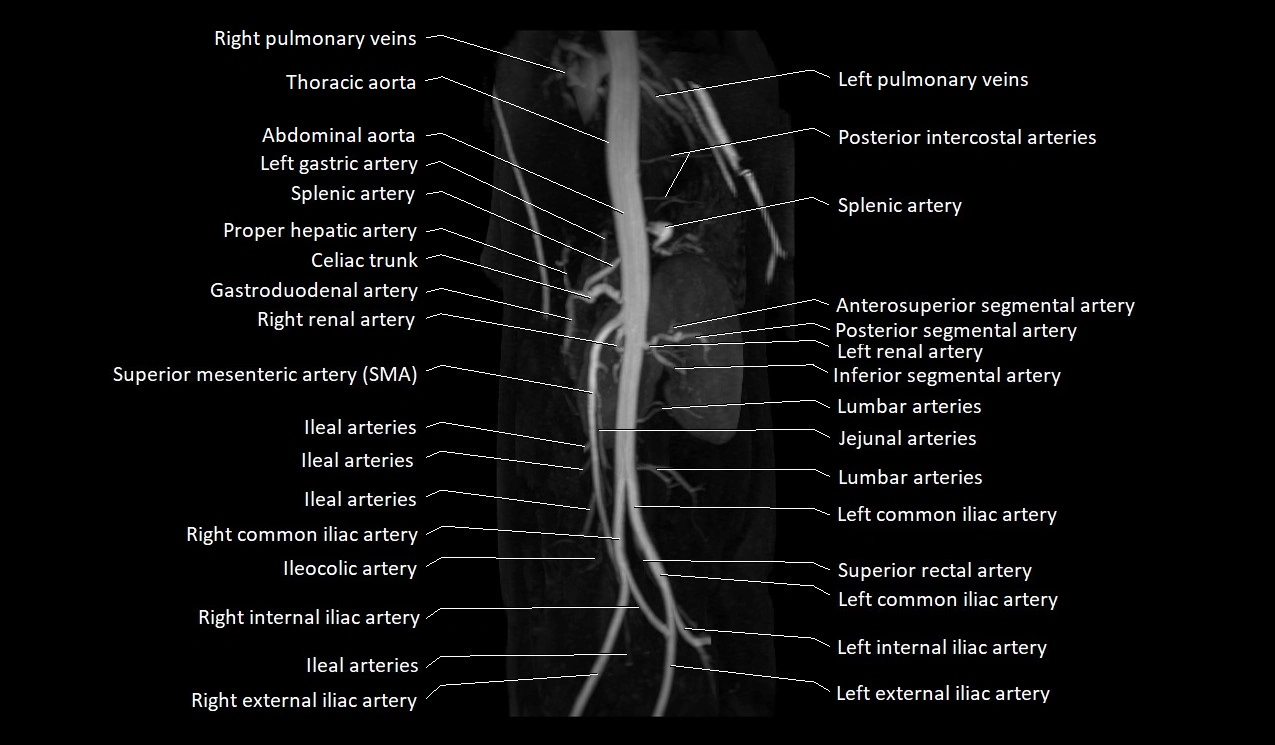

MRA (Magnetic Resonance Angiography):

• Contrast-enhanced MRA provides high-resolution imaging of the aorta and its branches

• Allows 3D reconstruction of visceral, parietal, and terminal branches

• Excellent for evaluating aneurysm size, dissection flap, stenosis, or preoperative planning

• Non-invasive alternative to conventional angiography